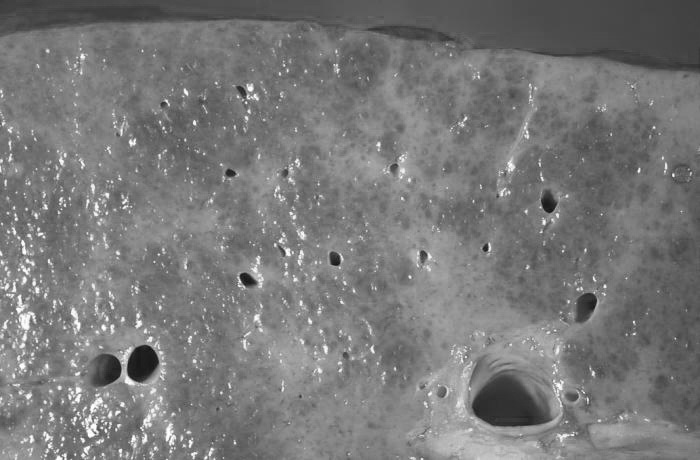

图为酒精性肝硬化的解剖切面。来源:PHIL

它只是各种因素导致肝细胞坏死、再生,肝星状细胞活化、增生后,“缠绕”再生肝细胞或残存肝细胞形成再生结节,逐步引起肝内血管(尤其是门静脉)、胆管等受压狭窄,形成门静脉系统的梗阻、高压扩张、改道等病变。